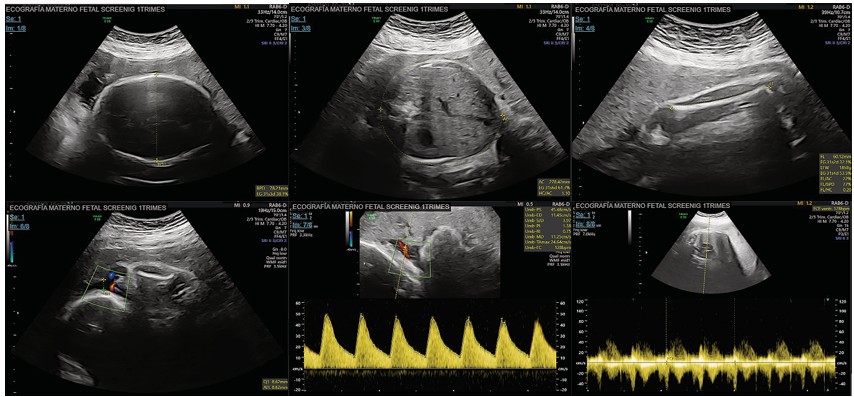

Paciente de 37 años sin antecedentes patológicos personales ni gineco-obstétricos relevantes, que acude para valoración por emergencia cursando embarazo de 31 semanas y 3 días de edad gestacional por fecha de última menstruación de su primer embarazo, producto de fertilización in-vitro, con la preocupación de salida de líquido claro por vagina en abundante cantidad, dos horas previo a su valoración sin presentar síntomas acompañantes. Al examen físico presenta un útero gestante, feto único vivo, transverso dorso superior, altura de fondo uterina acorde a edad gestacional, actividad uterina clínicamente ausente, frecuencia cardiaca fetal con 134 latidos por minuto, movimientos fetales presentes, genitales externos de nulípara, a la especuloscopía se evidencia cérvix central cerrado con hidrorrea macroscópica con líquido claro sin grumos en abundante cantidad, tacto vaginal diferido. Monitoreo electrónico fetal categoría I sin actividad uterina. Se administra primera dosis de maduración pulmonar con betametasona 12 miligramos intramuscular, se realiza ecografía obstétrica con frecuencia cardiaca fetal de 128 latidos por minuto, presentación transversa dorso superior, con biometrías acordes a la edad gestacional, peso fetal estimado de 1859 (±271 gramos) percentil 65, placenta anterior, se identifica líquido amniótico disminuido con bolsillo vertical máximo de 0.8 cm (Figura 1), sexo masculino. Se realizan exámenes de laboratorio con reporte de leucocitos 9.72 K/uL, neutrófilos 82.2%, linfocitos 10.8%, plaquetas 198.000 K/uL, hemoglobina13.9 g/dL, hematocrito 40%, proteína C reactiva 4.80 mg/L, interleucina-6 3.19 pg/mL, elemental y microscópico de orina no infeccioso, cultivo para estreptococo grupo B negativo.

Figura 1. Ecografía obstétrica al ingreso de la paciente. A) BDP: 78.2 mm. B) PA:278.4 mm. C) LF: 60.1 mm. D) Bolsillo máximo 0.8 cm. E) Doppler AU: percentil 89. F) FCF: 128 lpm.

Fuente. Imagen tomada de reporte ecográfico realizado en el Hospital Metropolitano de Quito, 2024